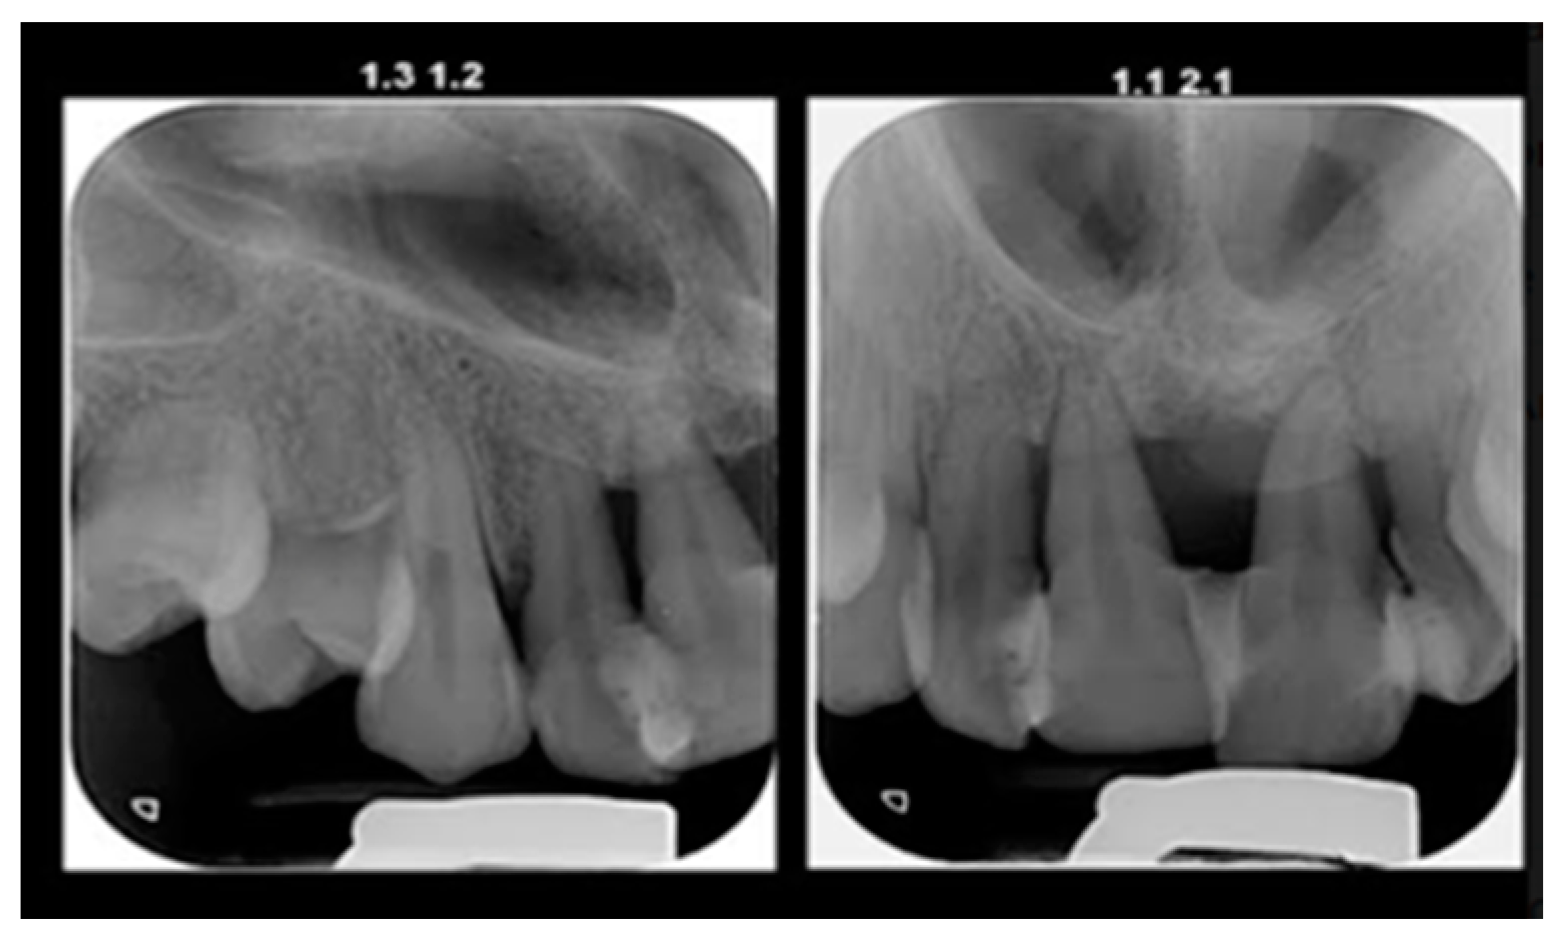

The initial radiography showed severe bone loss on the maxillary anterior tooth (Figure 3). In addition to the periodontal aspects, dental malposition of the maxillary and mandibular central and lateral incisors, deep bite malocclusion, deep hard palate, and advanced carious lesion in both maxillary first molars were observed. It was also not possible to specify whether the bone resorption in the anterior area was related to the trauma, considering that after the trauma, the patient did not request dental treatment.

Figure 3.

Initial panoramic radiograph.